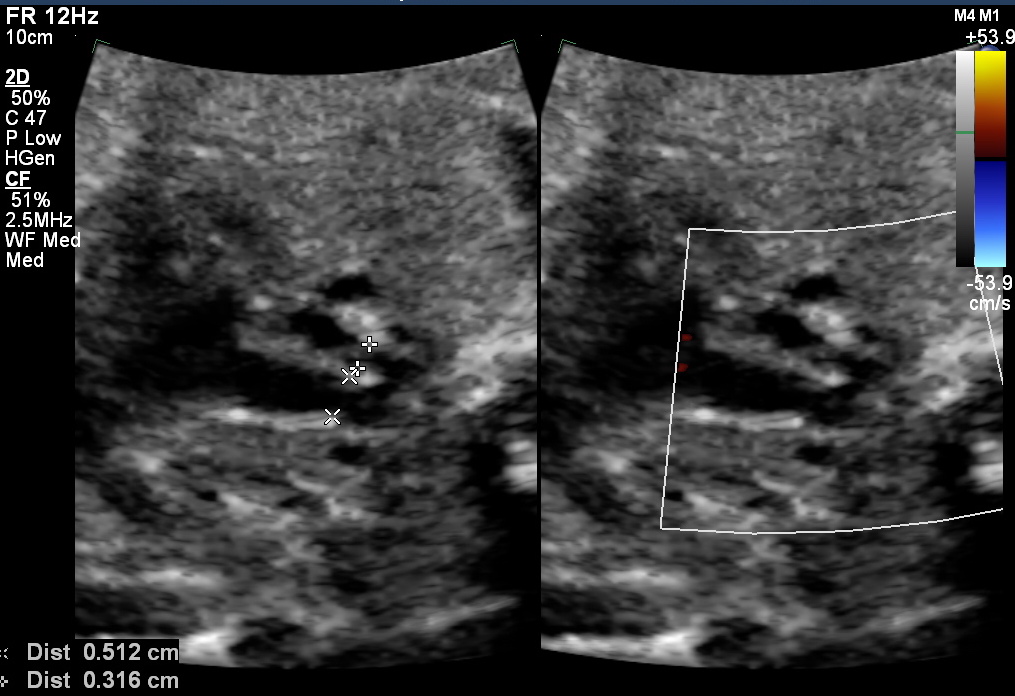

ID ratio is of significant interest because it is a relatively duration-independent parameter and it has significantly better specificity and positive predictive value. In the three vessels trachea view (3VT view), the internal diameter of the aortic isthmus was measured immediately proximal to the insertion of the ductus arteriosus and ductus at the distal-most point near insertion to descending aorta, inner margin to inner margin.

Matsui et al. showed that the isthmus to ductal ratio enabled good separation between their two groups. They used the 95% reference range of 0.74 to 1.23 for normal fetuses and an isthmus/ ductal ratio of < 0.74 for all fetuses who required surgery or surveillance after birth.

Study Gómez-Montes showed mean isthmus to the ductal ratio in normal fetuses of >0.7 and fetuses with post-natal coarctation it is <0.6 before 28 weeks and 0.5 in >28 weeks.

A retrospective study by Toole et al stated that an isthmus to the ductal ratio of <0.64 on any single fetal echocardiogram was nearly 90% sensitive and that <0.5 was 100% specific for postnatal coarctation.

Overall isthmus to ductal ratio is a good screening marker. When the ratio is above 0.74 without another additional marker of fetal coarctation, then the possibility of fetal coarctation is low. When the isthmus to ductal ratio is less than 0.74, the possibility of coarctation should be kept in the diagnosis. If the ratio is less than 0.6 in the first and second trimesters and less than 0.5 in the third trimester, the chance of CoA is very high. The parents in this situation should be counselled accordingly and delivery at a centre equipped with a pediatric cardiac unit should be recommended.